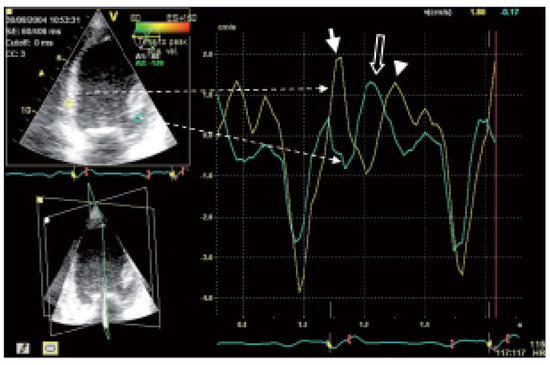

Biventricular pacing is an accepted therapy in patients suffering from terminal heart failure. Main obstacle however is the positioning of the left ventricular electrode via coronary sinus as well as its reliable fixation. This article describes in a...